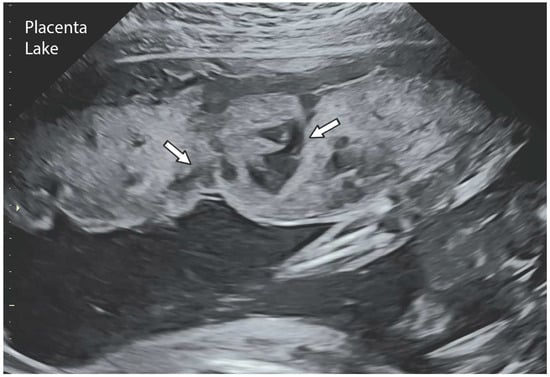

| Characteristics | Placental Lake | Placental Lacunae |

|---|---|---|

| Sonographic appearance | Anechoic area surrounded by normal tissue | Anechoic area surrounded by normal tissue |

| First ultrasound appearance | First trimester of pregnancy | Second trimester |

| Location | Areas of low villous density, under fetal plate, marginal areas | Distortion of placental lobular development around the prior uterine scar |

| Blood flow | Low volume or varying velocity | High volume and high velocity |